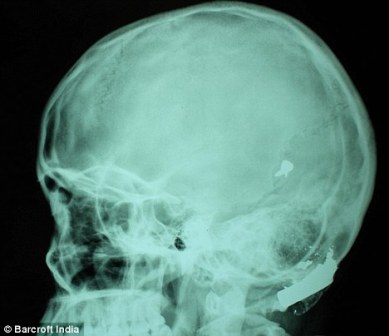

其中一顆子彈擊中她的左中耳,穿透了她的耳骨,然后擊中頭骨,嵌在了腦子里。另外兩顆子彈分別擊中她的右臂和心臟。印度Lok Nayak醫(yī)院的醫(yī)生稱,赫娜能夠康復(fù)完全是奇跡,她也足夠幸運。她的主治醫(yī)生稱:“當我們看到她的情況時,被嚇了一跳,幸運的是她活了下來。”

這顆子彈沒有損壞大腦中控制身體機能的部分。盡管赫娜的手術(shù)很成功,但醫(yī)生表示,她還有出現(xiàn)感染和并發(fā)癥的可能。子彈毀掉了她的中耳,可能導(dǎo)致她耳聾。(楊柳)